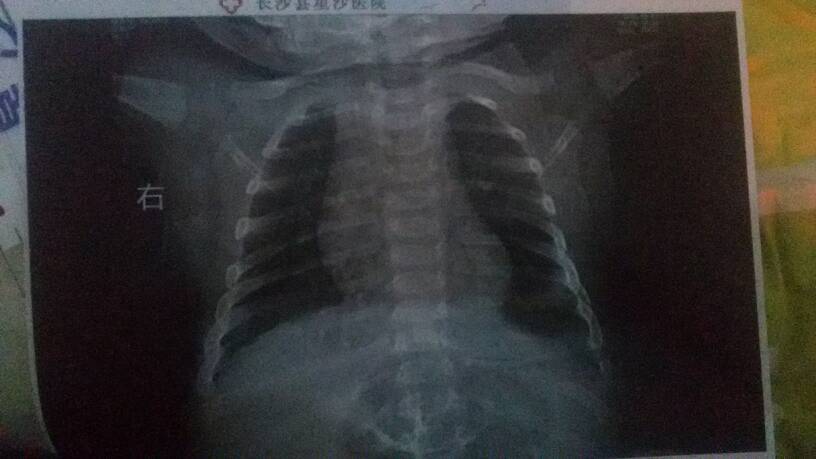

有医生在线吗,双肺呼吸音粗,可闻及少许湿罗音 是什么意识呀?这个片子,是正常的吗?

从描述上看考虑是支气管炎,你发上来的片上看双肺暂时没看到明显炎症,还有的是你发上的图不太清楚,或者换个相机拍清楚些发上来。。